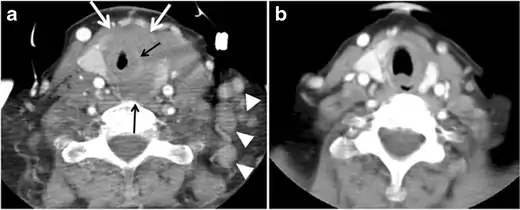

Fig. 6. A 61-year-old female patient with locally aggressive PTC. an Enhanced axial CT scan of the neck demonstrates a heterogeneous infiltrative thyroid mass. This mass diffusely involves the entire gland and circumferentially encases the trachea with involvement of bilateral tracheoesophageal grooves (white arrows). b, c Additional axial cranial images show right cricoid cartilage destruction (black arrows in b), right thyroid cartilage destruction (black arrow in c), right vocal cord paralysis (white arrows in b), and bilateral cervical lymphadenopathy (arrowheads).[1]